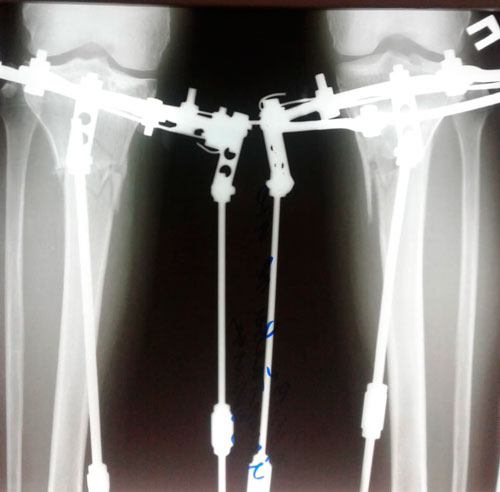

Ровные ножжки!

Re: Ровные ножжки!

Дата операции - 12.04.2019г

Дата снятия аппаратов - 25.07.2019.

Срок сращения- 103 дня.